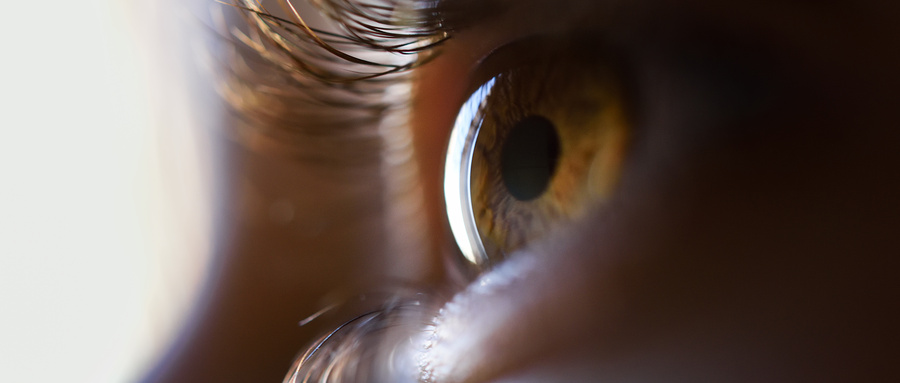

青光眼藥物治療有哪幾種

【文章導(dǎo)讀】青光眼治療的目的是保存患者的視功能,藥物治療是青光眼疾病的主要治療手段之一,也是應(yīng)用廣泛和便捷的治療方法。

青光眼治療的目的是保存患者的視功能,藥物治療是青光眼疾病的主要治療手段之一,也是應(yīng)用廣泛和便捷的治療方法。

藥物治療適合于幾乎所有類型青光眼(先天性青光眼不作為優(yōu)選)。包括開角型青光眼,閉角型青光眼,繼發(fā)性青光眼,高眼壓癥,術(shù)前控制眼壓,術(shù)后殘余性青光眼。